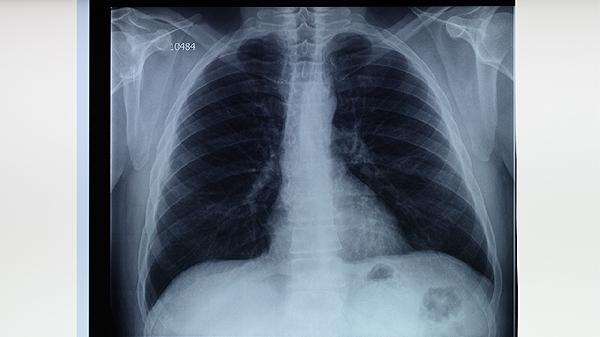

肺结核患者应严格遵循早期、联合、适量、规律、全程的用药原则,完成6-9个月的标准疗程。治疗期间保持高蛋白、高维生素饮食,适当补充牛奶、鸡蛋、瘦肉等优质蛋白。注意隔离消毒,咳嗽时用纸巾掩住口鼻,痰液需焚烧处理。定期复查胸部X线片和痰菌检查,出现药物不良反应及时就医调整方案。避免熬夜和过度劳累,适度进行呼吸功能锻炼有助于康复。